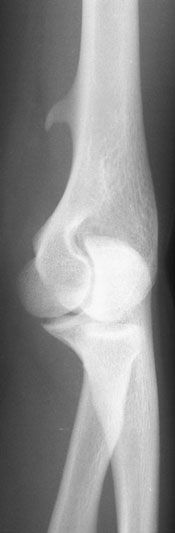

An otherwise healthy 16-year-old girl presented with medial arm pain after falling on her left elbow while skating. Robert P. Blereau, MD, and Timothy J. Haley, MD, of Morgan City, La, write that a radiograph of the left upper arm showed a spur projecting from the distal humerus; there was no fracture or dislocation.

A supracondylar process of the humerus (also known as supracondylar exostosis) is a normal developmental variant that affects approximately 1% of children. The bony spur develops on the medial aspect of the distal third of the humerus and looks like a beak that extends obliquely downward toward the elbow joint,unlike an osteochondroma, which points away from the joint.

Routine anteroposterior and lateral radiographs may not show the spur; an oblique radiograph provides the best view. The spur may be palpable.